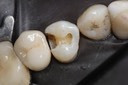

Gary Umeda #18, 19, 20 prep

Gary Umeda #18, 19, 20 try in